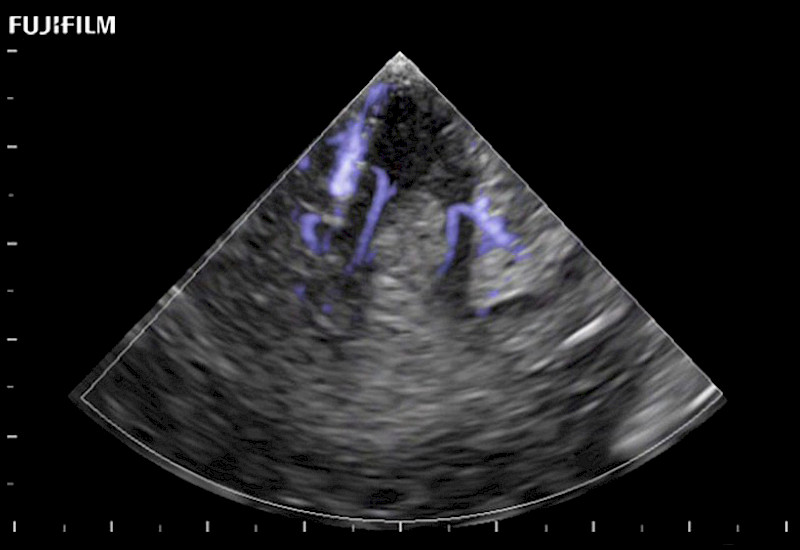

Tight curved (12mm) array transducer that is ideal for scanning during cranial guidance procedures.

Main Specifications: